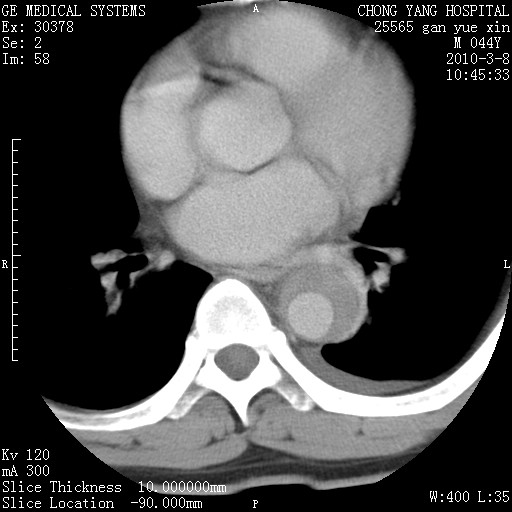

标题: CT24940:主动脉增强,典型病例。 [打印本页]

标题: CT24940:主动脉增强,典型病例。

夹层动脉瘤。

动脉夹层

夹层动脉瘤,典型

主动脉夹层。

动脉夹层的分型:

⒈debakey分型:根据主动脉夹层累及部位,分为三型:ⅰ型:原发破口位于升主动脉或主动脉弓部,夹层累及升主动脉、主动脉弓部、胸主动脉、腹主动脉大部或全部,少数可累及髂动脉。ⅱ型:原发破口位于升主动脉,夹层累及升主动脉,少数可累及部分主动脉弓。ⅲ型:原发破口位于左锁骨下动脉开口远端,根据夹层累及范围又分为ⅲa,ⅲb。ⅲa型:夹层累及胸主动脉。ⅲb型:夹层累及升主动脉、腹主动脉大部或全部。少数可累及髂动脉。

⒉stanford分型:a型:夹层累及升主动脉,无论远端范围如何。b型:夹层累及左锁骨下动脉开口以远的降主动脉。

夹层动脉瘤,少量胸水

夹层动脉瘤;左侧少量胸腔积液。

典型主动脉夹层。